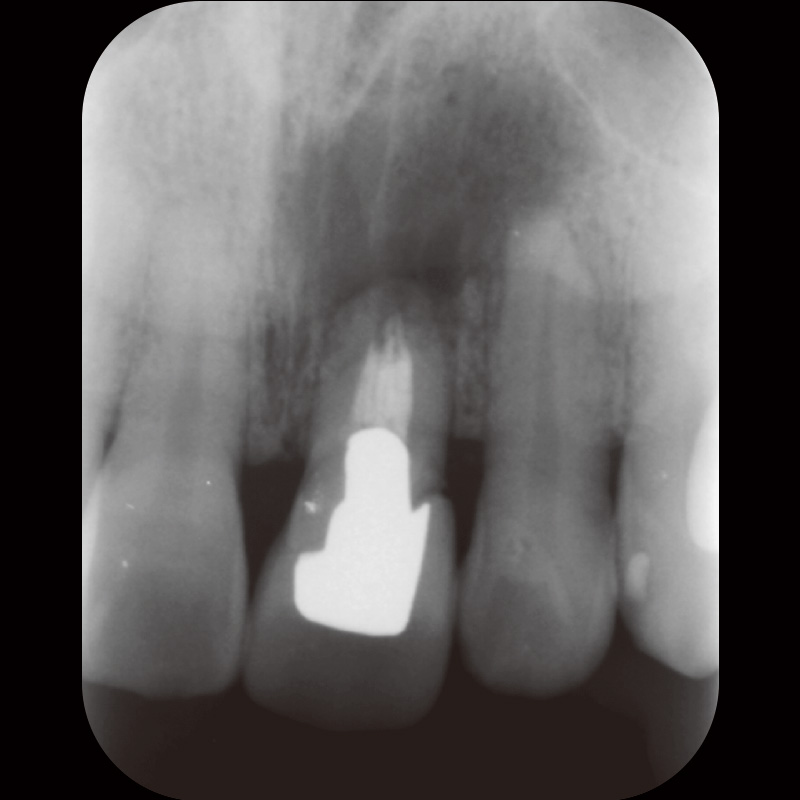

62歳女性で、₅に咬合痛があり近医にてメタルクラウンとメタルポストコアを除去したが、痛みと違和感が継続しているとのことで来院した。自発痛(-)咬合痛(+)・打診痛(+)・根尖部腫脹(-)根尖圧痛(軽度)であり、デンタルでは根尖部透過像・根尖孔外に突き出た根管充填材を認めた(症例2-1)。CBCTにおいても根尖孔外に突き出した根管充填材を認めた(症例2-2)。

症例2-1 初診時デンタルX線画像![[写真] 初診時CBCT画像](/academic/dentalmagazine/wp-content/uploads/sites/2/2025/11/195-6_photo08.jpg)